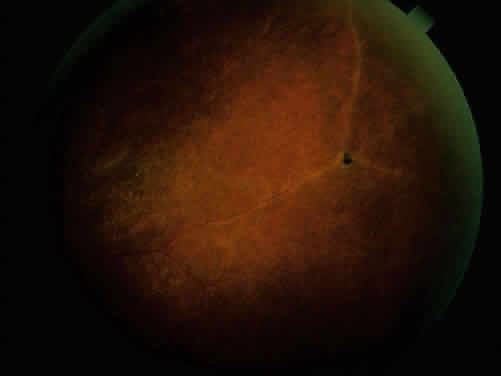

The conjunctivitis is usually described as mucopurulent and may be sterile. It may be accompanied by an iridocyclitis, episcleritis, or scleritis. Punctate and subepithelial corneal involvement has been reported. The iridocyclitis may be the presenting ocular manifestation. Recurrences are usually associated with an acute iridocyclitis, which is of rapid onset with conjunctival and episcleral edema and injection. The corneal endothelium has cellular debris and poorly defined, small-sized to medium-sized keratic precipitates.30 Heavy flare and cells and a very early tendency toward formation of posterior synechiae is characteristic, more so than in most other forms of acute iridocyclitis (Figs. 1, 2, and 3). Even the most aggressive pupil dilation management is sometimes inadequate for preventing synechiae. A peripheral iridectomy may be necessary to prevent iris bombé and angle closure if the synechiae cannot be broken enough to establish an opening for aqueous through the pupil (Fig. 4). The heavy flare is sometimes so plasmoid that cells are immobile and a fibrinlike clot may be seen in the pupil opening as the inflammation resolves. Cells and inflammatory debris may be seen in the vitreous, and blurring of the disc margins and macular edema may occur with severe or prolonged episodes. Lens clouding and posterior subcapsular cataracts occur with prolonged or repeated episodes. Hypotony can occur after a severe or prolonged course and may persist after resolution. Occasionally, secondary glaucoma may occur, owing to the anterior chamber reaction, in which case it will resolve as the inflammation resolves. With repeated recurrences, damage to the trabecular meshwork may occur, and prolonged recalcitrant glaucoma may result that may be poorly responsive to any medical or surgical management. This can be a serious factor in permanent visual loss with this type of iridocyclitis.15,16,30,31

Fig. 1. Early onset complete posterior synechiae in iridocyclitis with Reiter's disease.

Fig. 2. Partial dilation of pupil in Figure 1.

Fig. 3. Completed dilation of pupil in Figure 1 with pigment on anterior surface of the lens.